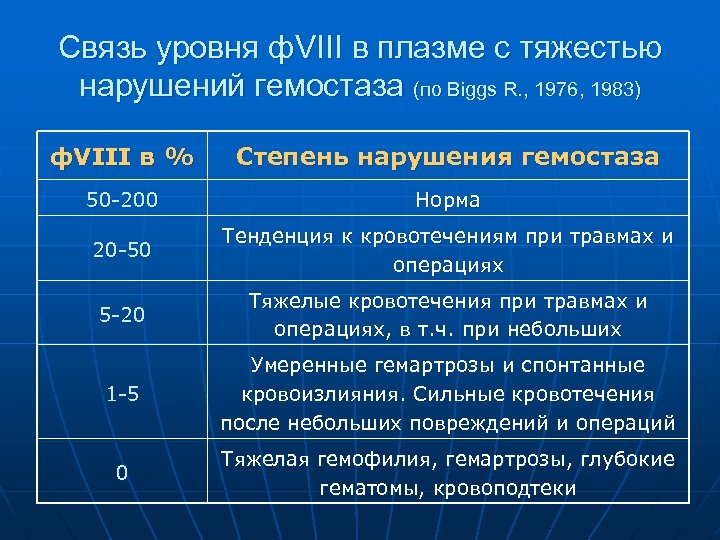

Связь уровня ф. VIII в плазме с тяжестью нарушений гемостаза (по Biggs R. , 1976, 1983) ф. VIII в % Степень нарушения гемостаза 50 -200 Норма 20 -50 Тенденция к кровотечениям при травмах и операциях 5 -20 Тяжелые кровотечения при травмах и операциях, в т. ч. при небольших 1 -5 Умеренные гемартрозы и спонтанные кровоизлияния. Сильные кровотечения после небольших повреждений и операций 0 Тяжелая гемофилия, гемартрозы, глубокие гематомы, кровоподтеки